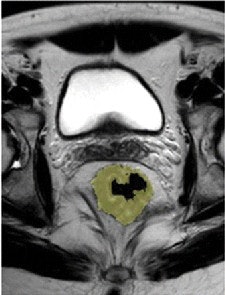

Pre- and post-treatment MRI was performed with a 1.5-tesla system (Intera R10, Philips Healthcare) using an eight-element pelvic phased-array surface coil. The subjects were imaged in the prone position after the placement of a thin rectal catheter in the rectum.

After initial localization imaging, researchers acquired MR images of the pelvis and rectum, with T2-weighted images obtained in the transverse, coronal, and sagittal planes during the scanning time of approximately 30 minutes.

The MR images calculated the mean tumor volume was 58 cm3 ± 75 before chemotherapy/radiation treatment and 20 cm3 ± 31 after therapy. The mean tumor volume reduction ratio in all patients was 68% ± 23.